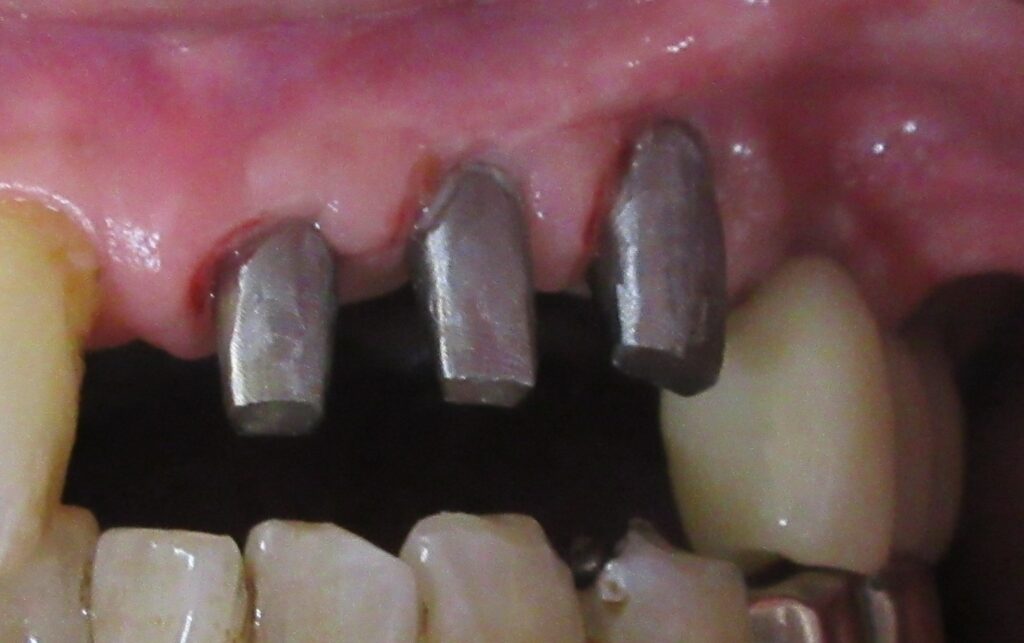

ドリルの先端を細い物から徐々に大きい物に変えながら、植立するインプラント体のネジの部分を除いた胴の部分の太さに合わせた大きさの穴を開けていきます。

開けた穴に、専用道具を使ってネジを締めるように長さ2センチ程のインプラントを骨に埋め込んでいきます。

続けて他の歯も同じように植立していきます。

インプラントオペでは、複数本を植立する場合でも、当時進行はせず、1本ずつ同じ工程を繰り返して植立します。